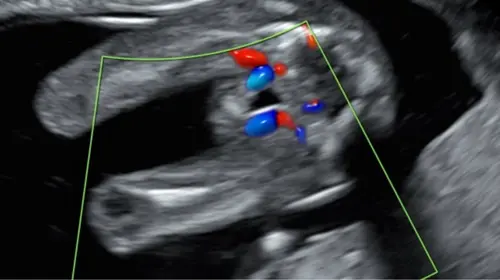

Foto 2

Nee dit is een jongen 馃挋

Ik denk (d茅nk) het omdat ik geen witte streep/strepen zie bij deze potty shot. De shot lijkt op de echo van ons zoontje. Wij krijgen nu een meisje en dat gaf een heel andere potty shot! Maar nogmaals, het is maar gissen. Veel plezier morgen en leuk als je het nog laat weten 馃挋馃┓

Ik denk een meisje omdat bij mijn zoontje bij dit shot er ballen een piemel tussen zat . Maarja durf het niet zeker te zeggen haha ;)